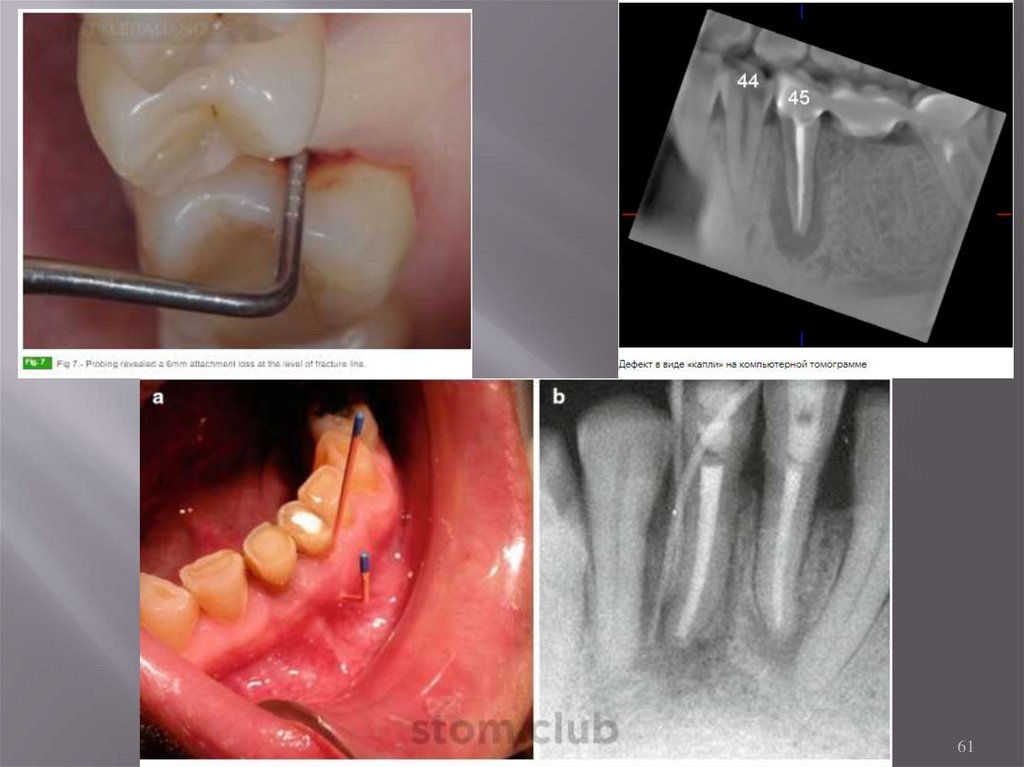

6.6. Клинические проявления

60

6.7 Диагностика

64